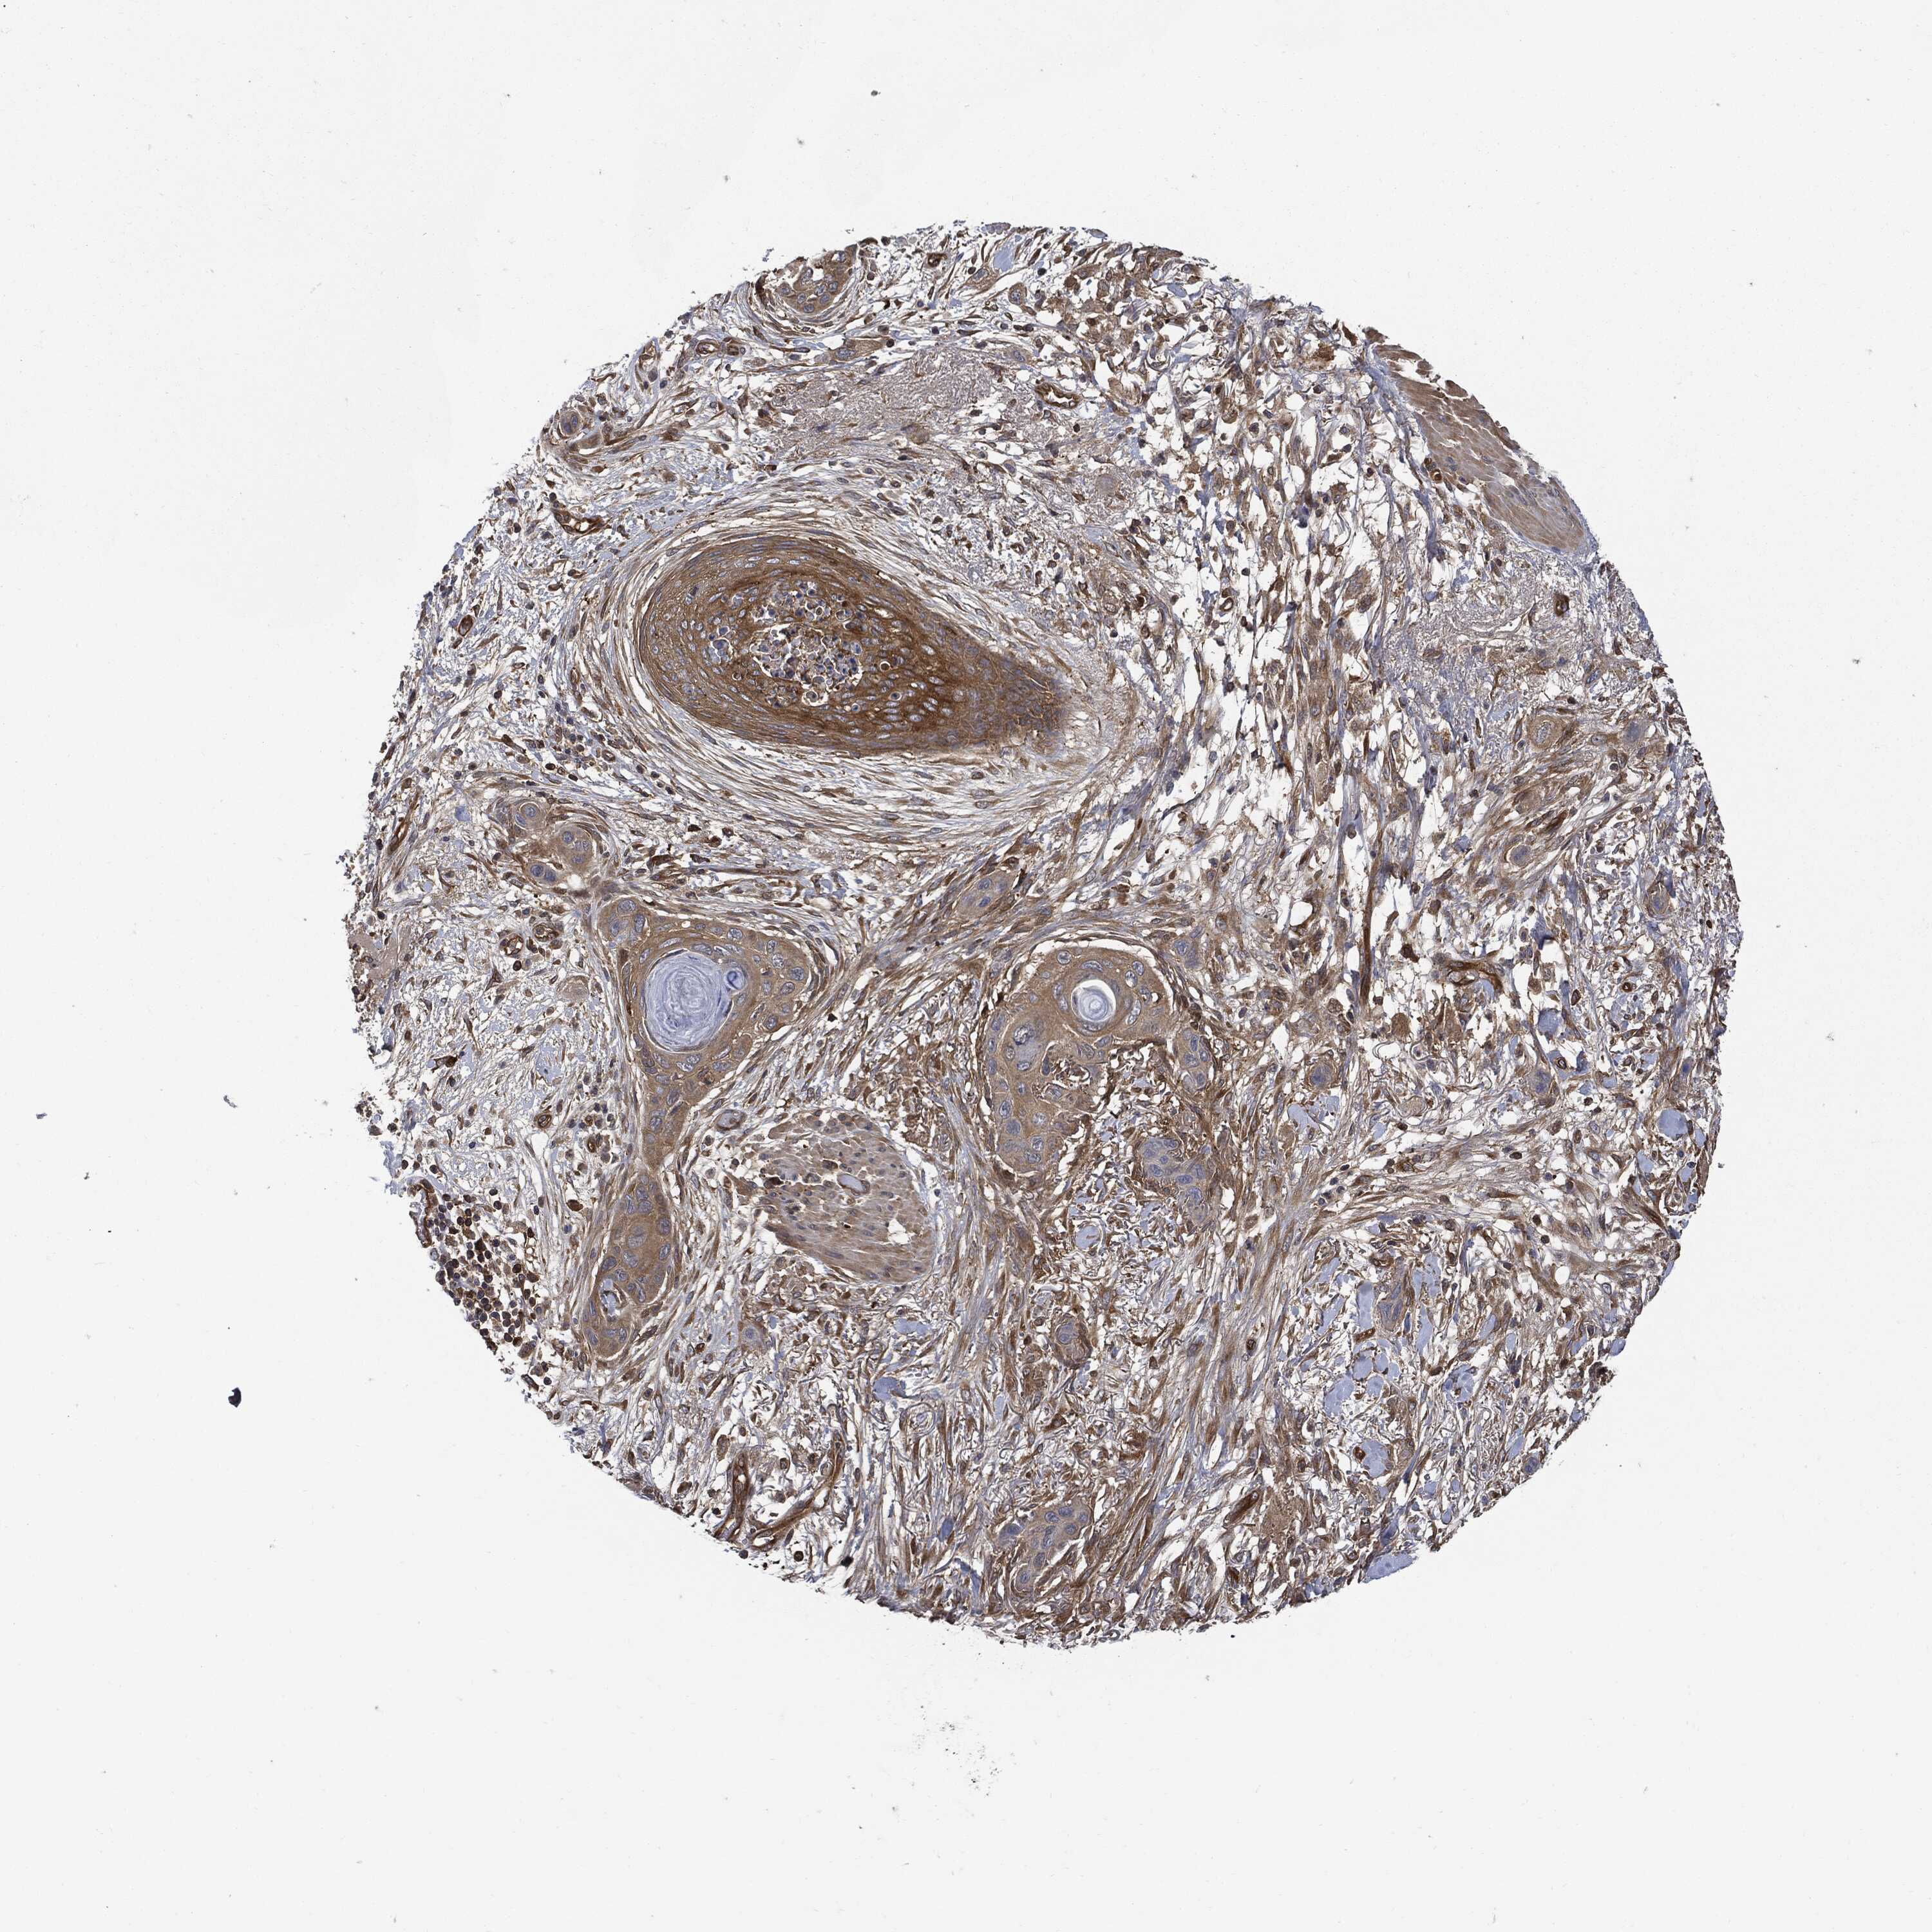

CANCER SKIN CANCER Show tissue menu

Basal cell and squamous cell cancer

SKIN CANCER - Protein expressioni

A mouse-over function shows sample information and annotation data. Click on an image to view it in a full screen mode. Samples can be filtered based on level of antibody staining by selecting one or several of the following categories: high, medium, low and not detected. The assay and annotation is described here.

Antibody stainingi

Antibody staining in the annotated cell types in the current human tissue is reported as not detected, low, medium, or high, based on conventional immunohistochemistry profiling in selected tissues. This score is based on the combination of the staining intensity and fraction of stained cells.

Each image is clickable and will lead to virtual microscopy that enables deeper exploration of all samples and also displays staining intensity scores, fraction scores and subcellular localization as well as patient and tissue information for each sample.

Squamous cell carcinoma, NOS